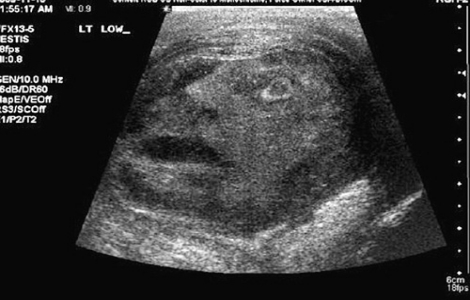

Mặt người kỳ lạ xuất hiện khi siêu âm khối u tinh hoàn một bệnh nhân ở Canada.

Bác sĩ G. Gregory Roberts và Naji J. Touma đến từ Đại học Queen ở Ontario, Canada trong lúc thực hiện loạt siêu âm để kiểm tra những bất thường ở tinh hoàn của một bệnh nhân 45 tuổi đã phát hiện hình ảnh mặt người kỳ lạ tại đó. Sự việc này hai vị bác sĩ cảm thấy vô cùng sửng sốt.

Hình ảnh trên máy quét siêu âm cho thấy một khuôn mặt có vẻ "đau khổ" với chiếc miệng há hốc đã xuất hiện trong khối u tinh hoàn của bệnh nhân. Hai bác sĩ G. Gregory Roberts và Naji J. Touma rất ngạc nhiên và họ đã gửi hình ảnh này lên Urology - tạp chí chính thức của Hiệp hội quốc tế về tiết niệu học.

Mặt người kỳ lạ xuất hiện khi siêu âm khối u tinh hoàn một bệnh nhân ở Canada |

Hai vị bác sĩ cho biết: "Chúng tôi và các nhân viên y tế đều hết sức sửng sốt khi thấy khuôn mặt của người đàn ông trong bức ảnh siêu âm. Khuôn mặt đó trông rất... đau khổ, như thể "anh ta" cũng có khối u tinh hoàn vậy."

Sau khi tình huống bất ngờ này xảy ra, những luồng ý kiến trái ngược đã nổ ra. Nhiều người cho rằng, đây là dấu hiệu của một vị thần nhưng đa số đều nhất trí rằng khuôn mặt đó chỉ là một sự trùng hợp ngẫu nhiên. Các bác sĩ đã cắt bỏ khối u tinh hoàn của bệnh nhân. Thật may mắn cho người đàn ông này vì đó chỉ là một khối u lành.